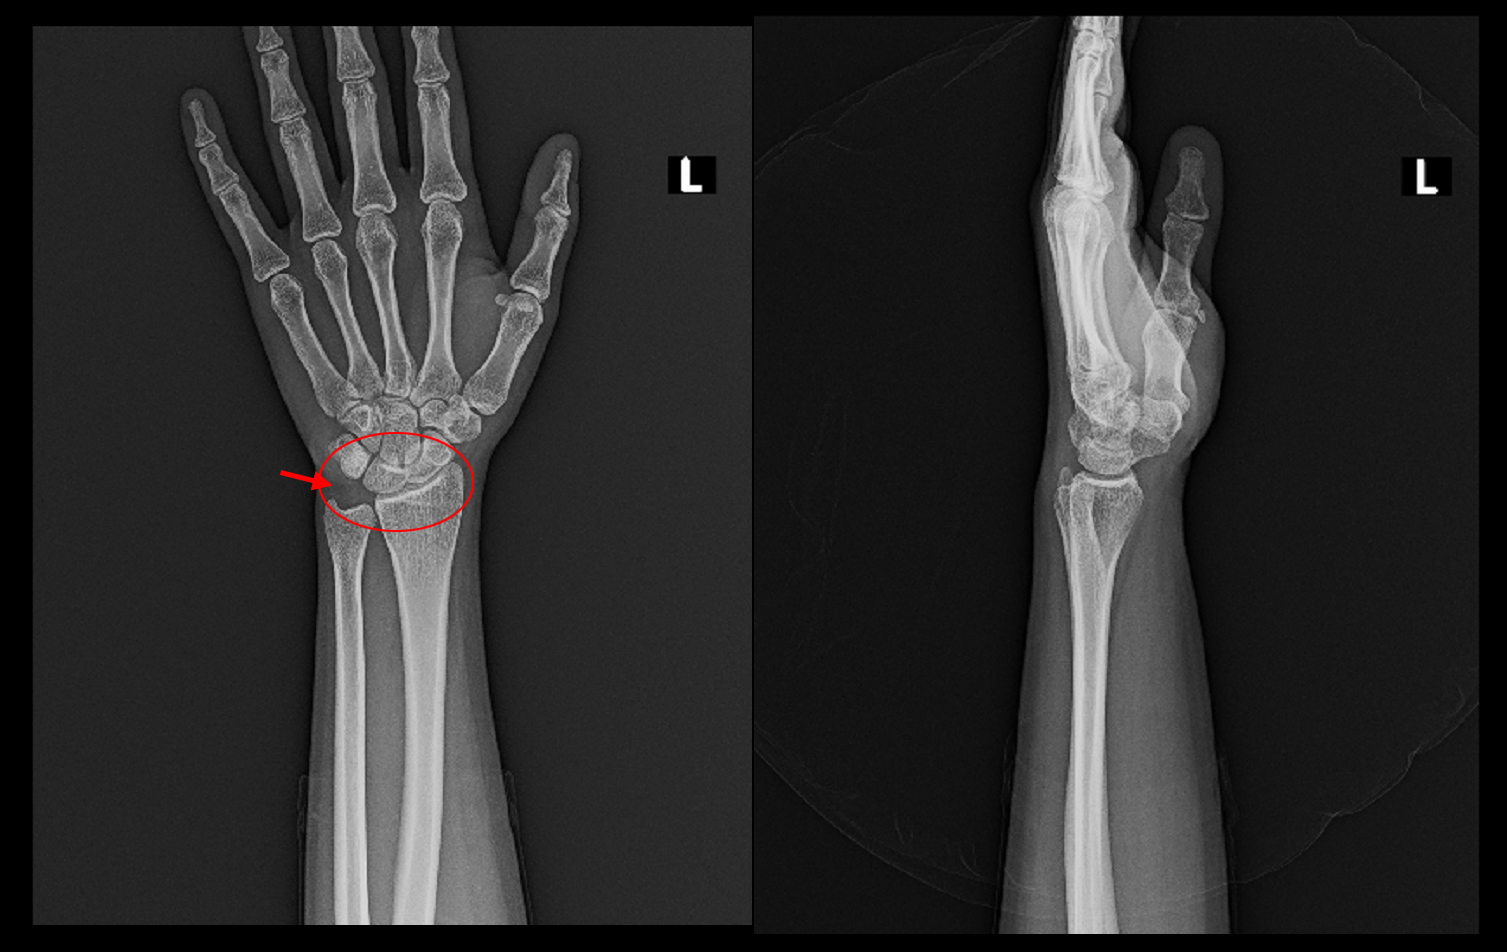

15才男 Xp.jpg

レントゲン像では異常を認めません。右手関節の橈骨(親指側の骨)と尺骨(小指側の骨)の間の遠位橈尺関節部と三角線維軟骨に圧痛を認めました。24才女性看護師に処方した薬と同じ薬を1週間処方し、多分それで良くなるでしょうと説明しました。